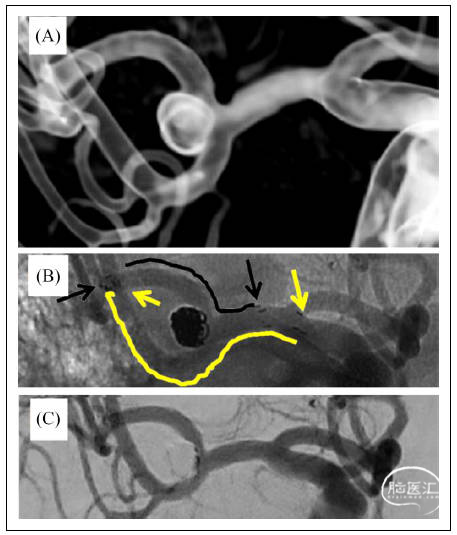

图1. 52岁头痛2周的右侧大脑中动脉瘤患者行Y型支架辅助栓塞